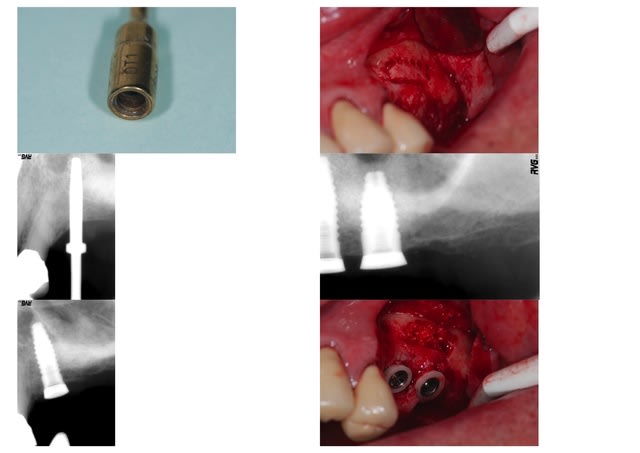

je vous livre le récit d'une petite mésaventure provoquée par la rupture d'un insert pendant la découpe du volet : le piezo s'est brusquement arrêté en affichant "err 5" et a refusé de redémarrer! il parait que c'est rare, l'insert s'est en fait félé (cet insert n'avait servi que 5 fois) ; la félure est visible sur la photo à fort grossissement au milieu du O gravé; mais quand on ne comprend pas ce qui se passe, c'est assez gênant, d'autant plus que j'étais en stérile, que le mode d'emploi ne l'était pas et qu'il était rangé dans son tiroir; sans expérience de ce genre de situation, j'ai cru que le piézo était en panne, alors qu'il suffisait de changer d'insert; j'ai donc continué avec le seul matériel stérile disponible : une petite fraise boule pour passer la corticale, et le CA du moteur chirurgical; la difficulté était évidemment de ne pas perforer la membrane avec cet équipement, mais comme elle était épaisse, j'ai donc quand même tenté le coup; ça a heureusement passé, ouf!

moralité, changer d'insert avant de croire que c'est le piezo qui est en panne, et toujours avoir une très grosse fraise boule sous la main si jamais il tombe vraiment en rade! bon lifts

la fracture interesse d'habitude l'extremité travaillante mais c'est la premiere fois que je vois une fêlure du métal à ce niveau...défaut de fabrication de l'insert en question?